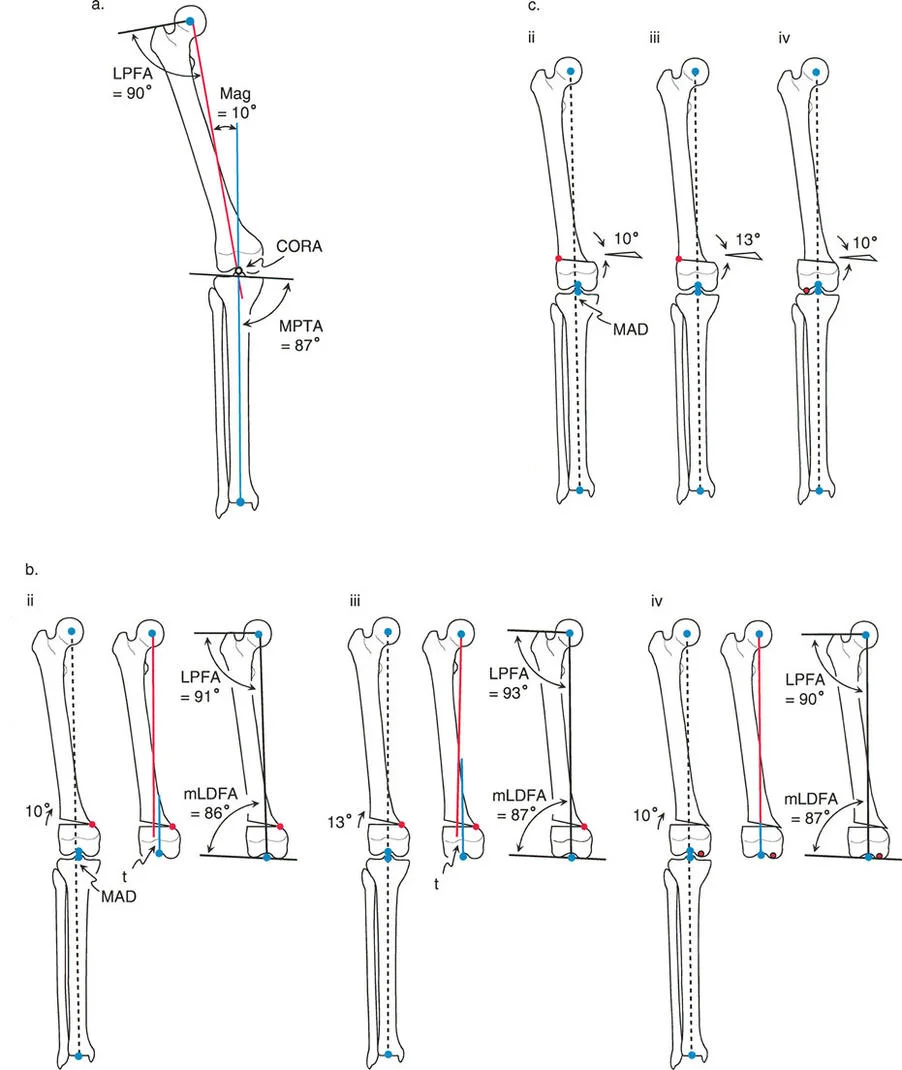

- mLDFA (mechanical Lateral Distal Femoral Angle) This is the lateral angle formed between the mechanical axis of the femur and the distal femoral joint line. The normal value is 87 degrees, with a standard range of 85 to 90 degrees. An mLDFA greater than 90 degrees indicates a distal femoral varus deformity. An mLDFA less than 85 degrees indicates a distal femoral valgus deformity.

- LPFA (Lateral Proximal Femoral Angle) This is the lateral angle formed between the mechanical axis of the femur and a line drawn from the tip of the greater trochanter to the center of the femoral head. The normal value is 90 degrees (range 85 to 95 degrees).

- MPTA (Mechanical Proximal Tibial Angle) This is the medial angle formed between the mechanical axis of the tibia and the proximal tibial joint line. The normal value is 87 degrees (range 85 to 90 degrees). An MPTA less than 85 degrees indicates proximal tibial varus. An MPTA greater than 90 degrees indicates proximal tibial valgus.

The Center of Rotation of Angulation (CORA) represents the apex of the deformity. To find the CORA, the surgeon draws the Proximal Mechanical Axis (PMA) line and the Distal Mechanical Axis (DMA) line.

* The PMA is drawn by taking the normal joint orientation angle from the proximal joint and extending a line down the shaft.

* The DMA is drawn by taking the normal joint orientation angle from the distal joint and extending a line up the shaft.

* The exact point where the PMA and DMA intersect is the CORA.

Osteotomy Rule One Pure Angulation

When the osteotomy line and the ACA both pass directly through the CORA, pure angular correction is achieved.

The Biomechanical Result

The mechanical axis is fully restored to normal. Because the bone is cut exactly at the apex of the deformity and hinged at that exact same apex, there is no translation of the bone segments. The anatomic axis realigns perfectly without any "step-off" or cortical bump. The proximal and distal bone segments will have maximum bony contact, promoting rapid union.

Osteotomy Rule Two Angulation with Translation

When the ACA passes through the CORA, but the osteotomy line is made at a different level (either proximal or distal to the CORA).

The Biomechanical Result

The mechanical axis and joint orientation angles are perfectly restored. However, because the bone cut is made at a distance from the hinge point, the bone segments will mathematically translate relative to one another. This creates a visible "bump" or step-off in the anatomic axis. While the bone looks jagged on an x-ray, the load-bearing mechanical axis is flawless.

Osteotomy Rule Three Secondary Deformity

When the osteotomy line and the ACA are both placed at a level different from the CORA.

The Biomechanical Result

A secondary translational deformity is created. While the angular deformity may appear to be corrected, the mechanical axis will not be fully restored. The proximal and distal mechanical axes will be parallel but not collinear, resulting in residual Mechanical Axis Deviation (MAD).